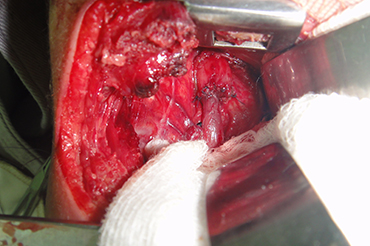

Atresia de Esofago

Neonatal y Lactante